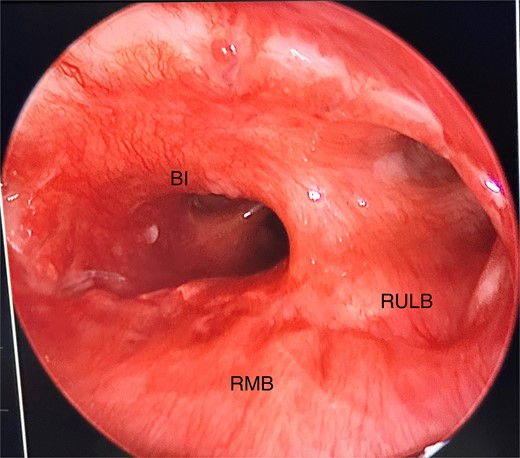

Anomalous right bronchial anatomy was also noted (Fig. 3). The biopsy was sent for frozen section, which confirmed a carcinoid tumour.

Post disobliteration of the tumour through rigid bronchoscopy, also showing aberrant anatomy, where the apical segmental bronchus of the right upper lobe has a high take off at the distal trachea/carina; C, carina; RMB, right main bronchus; BI bronchus intermedius; RULB, right upper lobe bronchus; ASB, apical segmental bronchus.